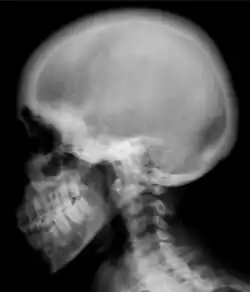

Ground glass density of the skull.[18] -

Renal osteodystrophy is usually diagnosed after treatment for end-stage kidney disease begins; however the CKD-MBD starts early in the course of CKD.[1][6] In advanced stages, blood tests will indicate decreased calcium and calcitriol (vitamin D) and increased phosphate, and parathyroid hormone levels. In earlier stages, serum calcium, phosphate levels are normal at the expense of high parathyroid hormone and fibroblast growth factor-23 levels. X-rays will also show bone features of renal osteodystrophy (subperiostic bone resorption, chondrocalcinosis at the knees and pubic symphysis, osteopenia and bone fractures) but may be difficult to differentiate from other conditions. Since the diagnosis of these bone abnormalities cannot be obtained correctly by clinical, biochemical, and imaging methods (including measurement of bone-mineral density), bone biopsy has been, and still remains, the gold standard analysis for assessing the exact type of renal osteodystrophy.[6][16]